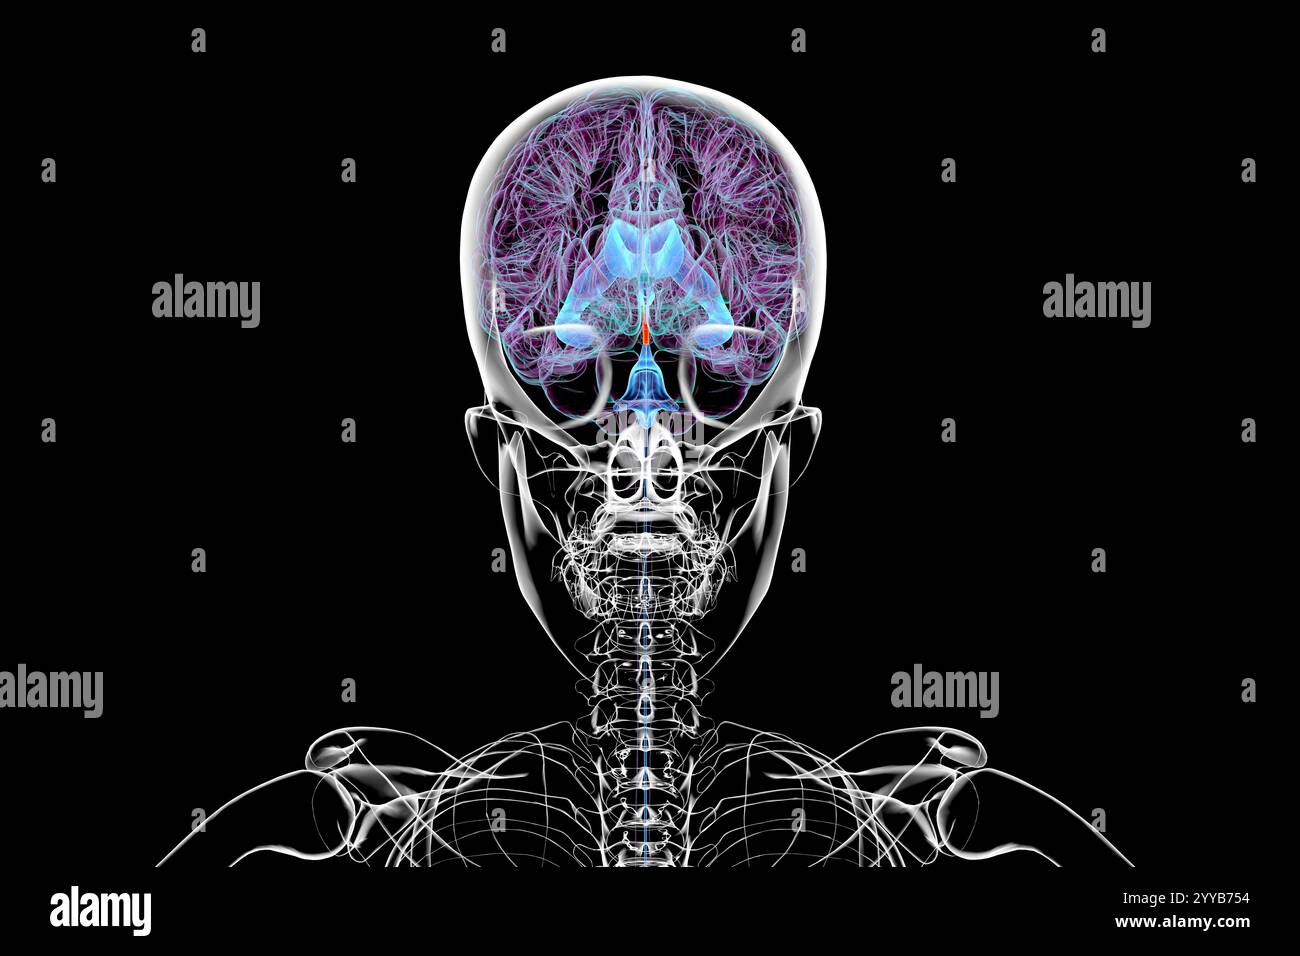

RF2T7NGWK–Ventrikel und zerebraler Aquädukt lateral in Farben Röntgenbild-3D-Rendering-Illustration. Menschliches Gehirn und Ventrikelsystem Anatomie, medizinisch, gesund

RF2T6AR8J–3D-Rendering-Illustration für die Röntgenansicht des Gehirns oder des Sylvius aquädukt. Anatomie des menschlichen Gehirns und des Ventrikelsystems, Medizin, Gesundheitswesen, Biologie, Wissenschaft,

RF2T030GG–Röntgenlaterale Darstellung der Hirnventrikel 3D-Darstellung mit Körperkonturen. Anatomie des menschlichen und ventrikulären Systems, Medizin, Biologie, Scienc